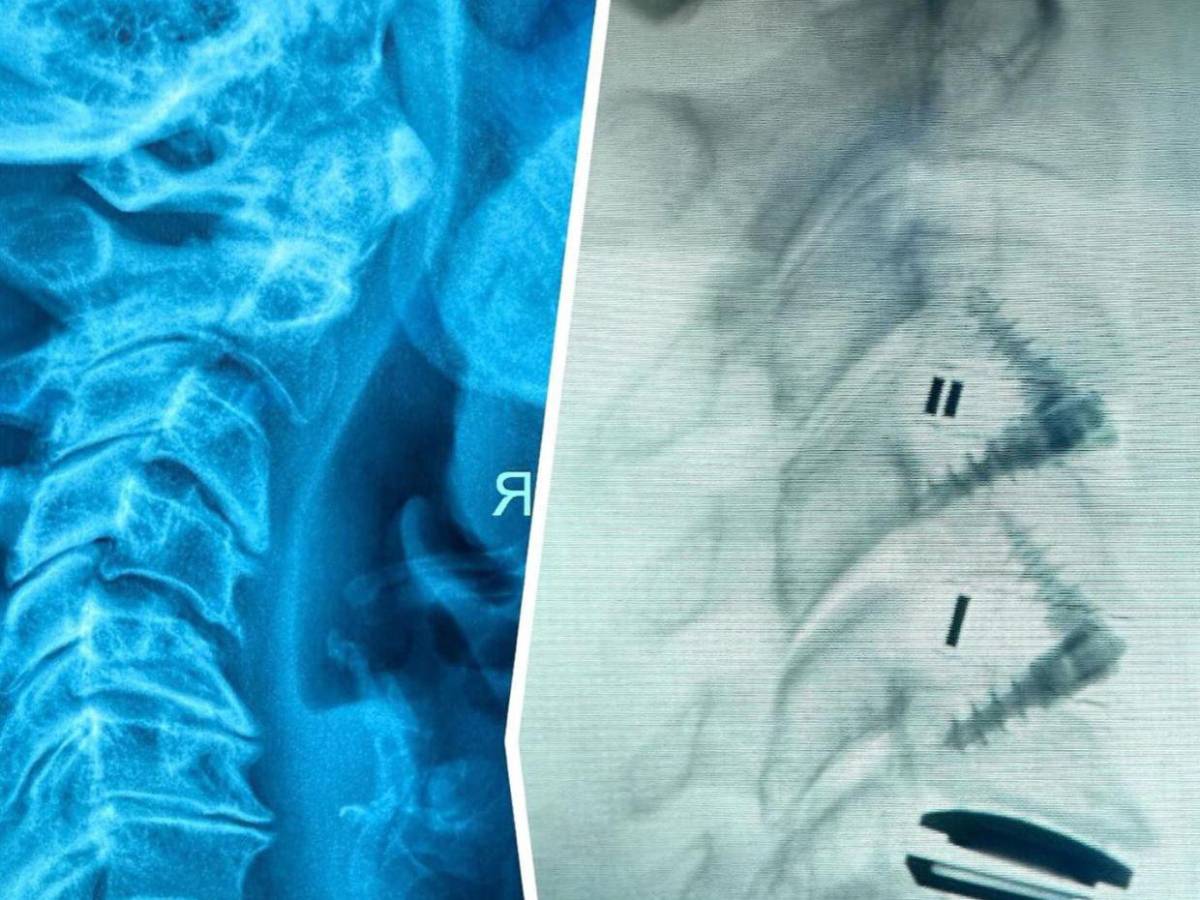

Según informaciones médicas recientes, la cantante padece hernias discales que requieren tratamiento especializado. Esta patología, que afecta al disco intervertebral cuando su núcleo pulposo se desplaza y ejerce presión sobre las raíces nerviosas, provoca dolor intenso en los pacientes.

La solidificación del material inyectado ha provocado dolores persistentes en la región lumbar y las extremidades inferiores, lo que ha obligado a la artista a someterse a más de cuarenta procedimientos quirúrgicos para extraer fragmentos del compuesto.